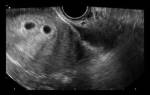

Единственный надежный способ подтвердить беременность двойней – это ультразвуковое исследование. Поэтому многие женщины не знают об этом до первого ультразвукового сканирования через 10-13 недель после зачатия. Однако следует учесть, если плодов больше двух, становится сложнее точно определить их количество.

В случаях осложнений беременности, таких как кровотечение, или после лечения бесплодия, первое ультразвуковое исследование будет, скорее всего, через 6 недель. Однако на данном этапе трудно заметить два плода. Изредка бывает, что при зачатии у женщины наступает беременность двойней, но в дальнейшем развивается только один плод. Это известно как синдром «исчезающего близнеца».

4. Ультразвуковое исследование — самый достоверный способ увидеть и определить, какая у женщины беременность, более точный срок беременности, размеры плодов и все патологии, существующие у двоих эмбрионов (если таковые имеются). А также при помощи данного метода возможно определить однояйцевая или разнояйцевая беременность наблюдается у женщины.

Двойню на УЗИ можно увидеть и определить уже на 4-5 неделе беременности. Как правило, однояйцевые близнецы определяются позже, чем разнояйцевые (не раньше 12 недели).

Самый ранний срок, когда по УЗИ различим плодный мешочек – это 4 недели и 3 дня при условии, что менструальный цикл женщины 28 – 30 дней. Но двойню пока никакой аппарат не определит. Это возможно лишь на 8 акушерской неделе.